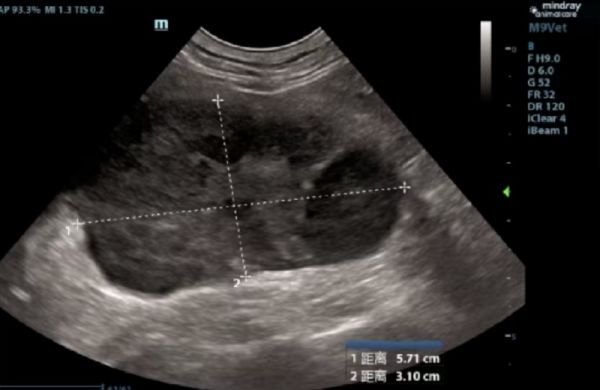

此前,一只8岁的猫咪因食欲下降、体重减轻就诊,经超声检查发现腹腔内有两处明显肿块,因肿物位于肾脏且猫咪体况较差,直接开腹进行病理检查损伤较大,石晶院长根据临床经验建议主人进行细针抽吸、血液检查等。细胞学检查确诊为肾脏淋巴瘤。随即进行化疗治疗,治疗后肾脏内肿瘤大小明显好转。